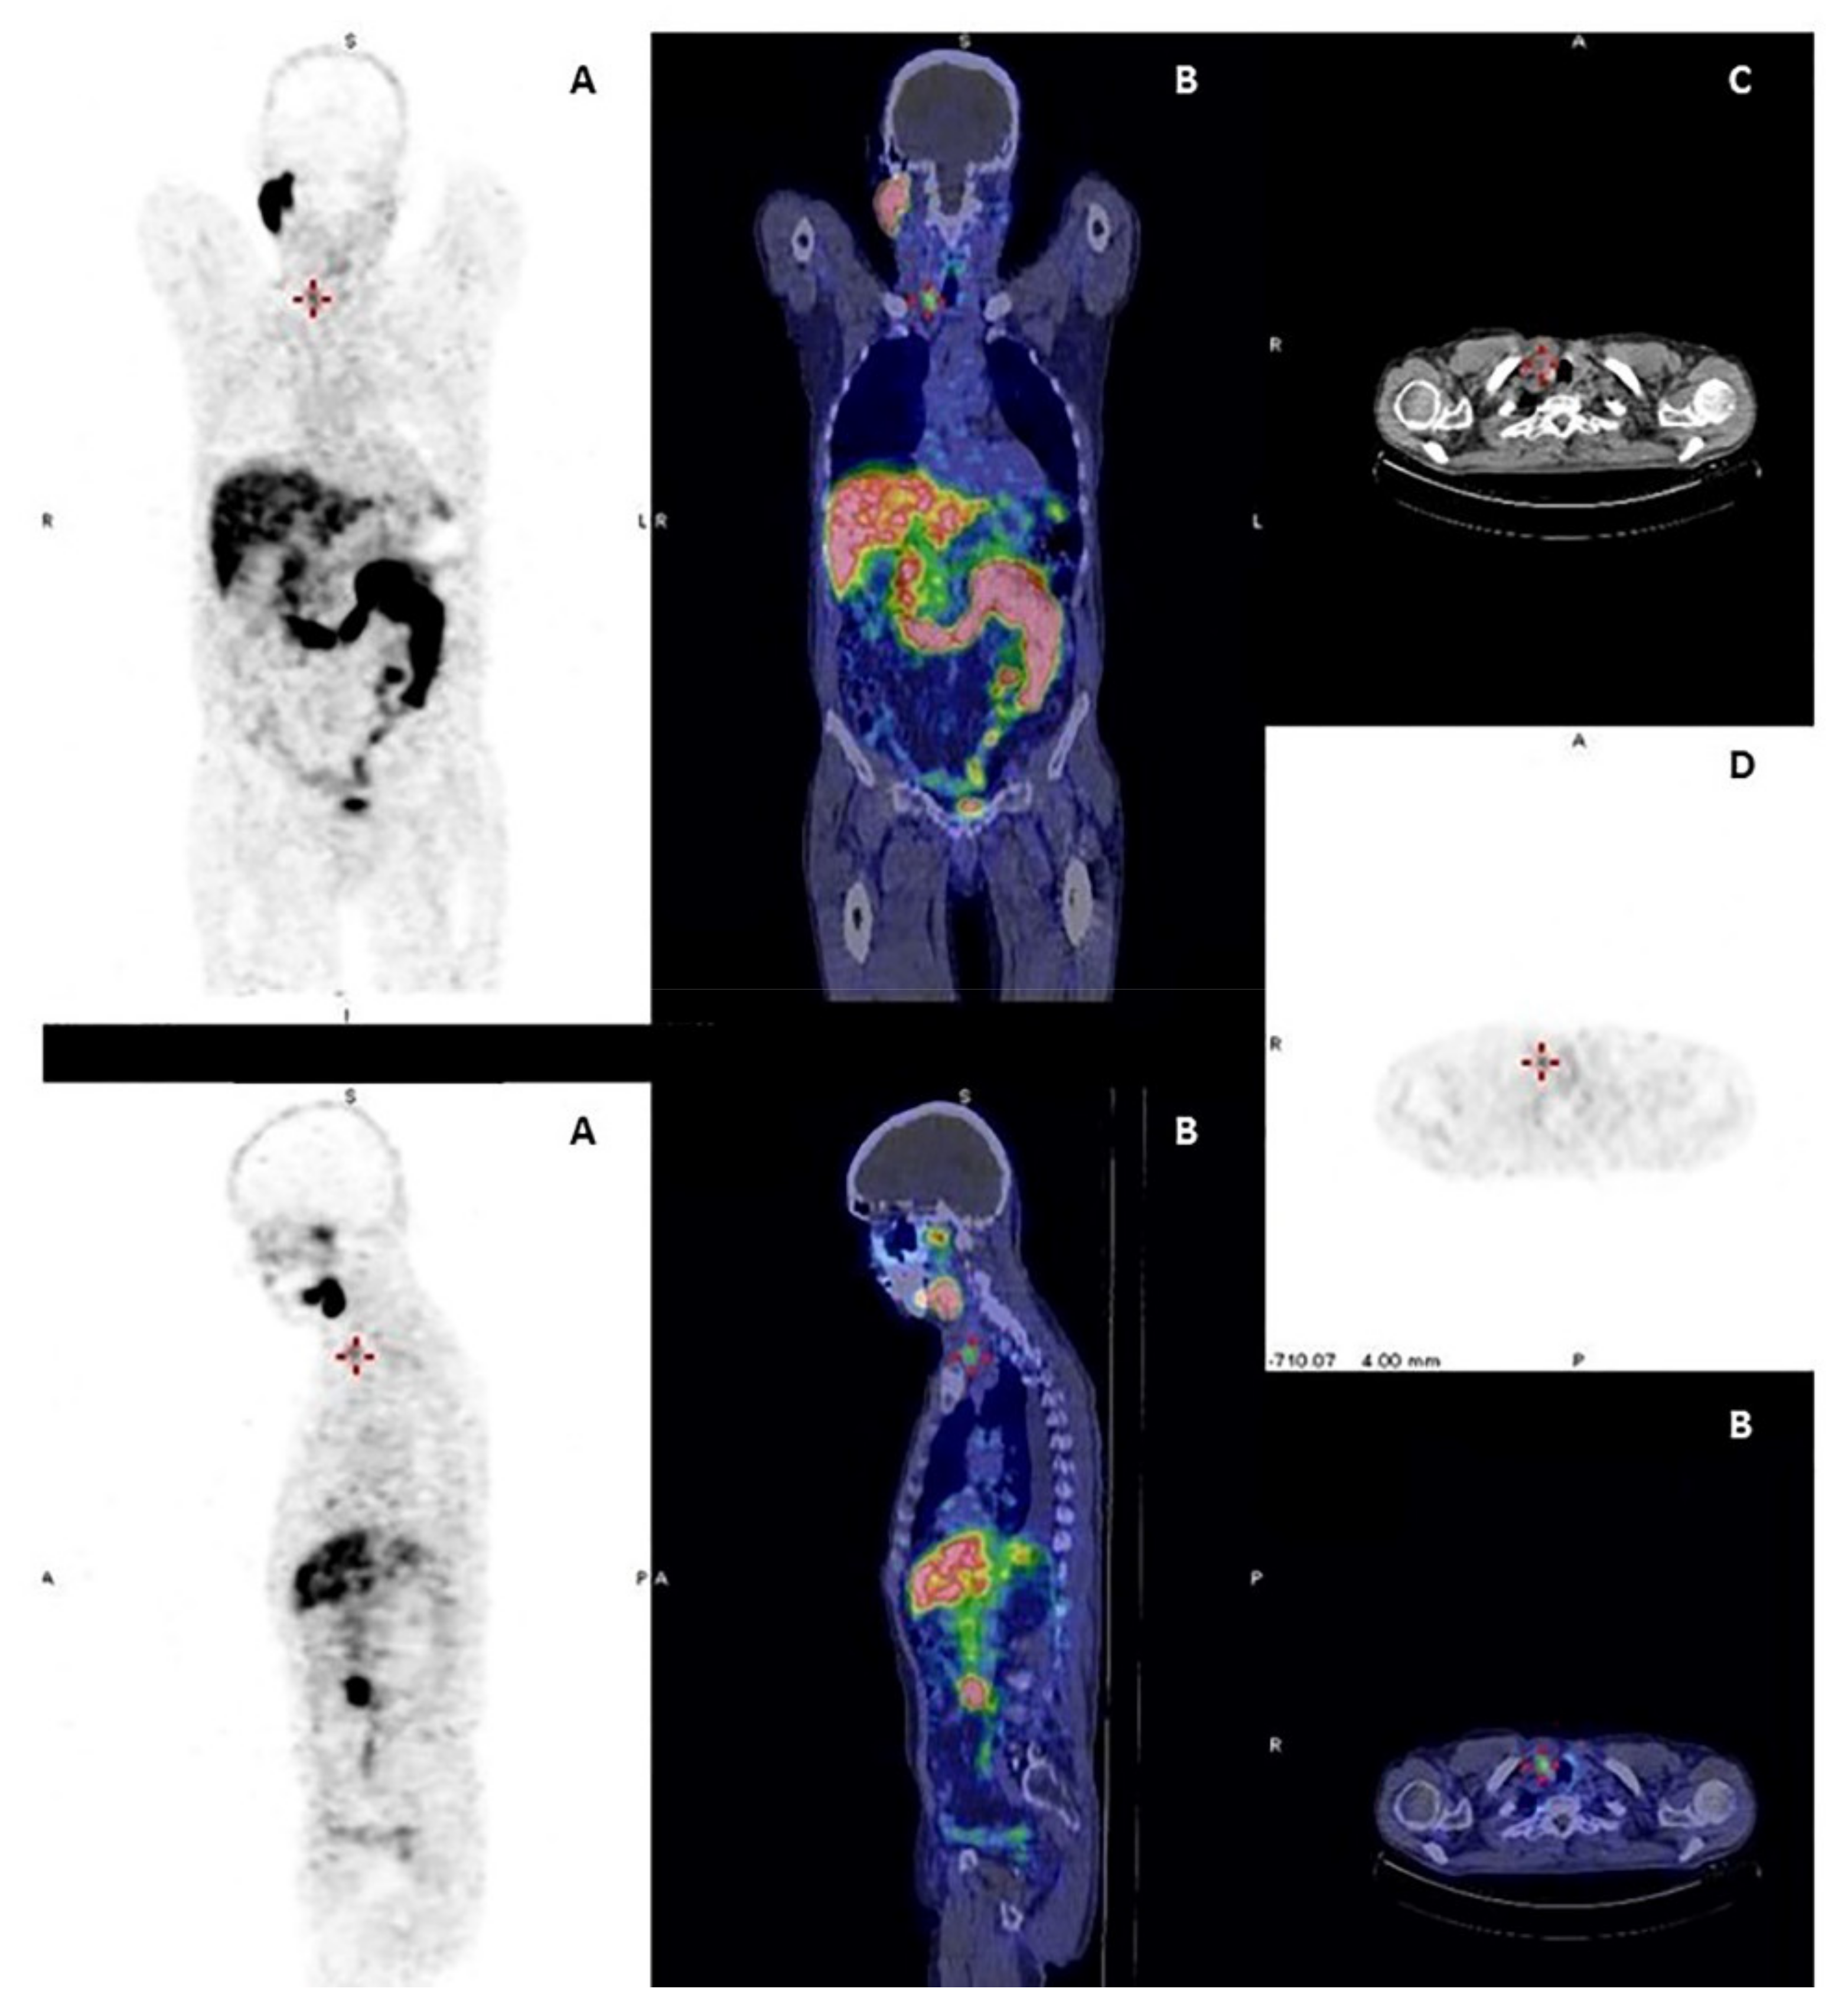

Thyroid Cancer Explore vol.3 no.2(2201 「Thyroid Cancer Expl。Thyroid Cancer | SpringerLink。Advances in Functional Imaging of Differentiated Thyroid Cancer。

Thyroid crisis caused by metastatic thyroid cancer: an

Thyroid crisis caused by metastatic thyroid cancer: an